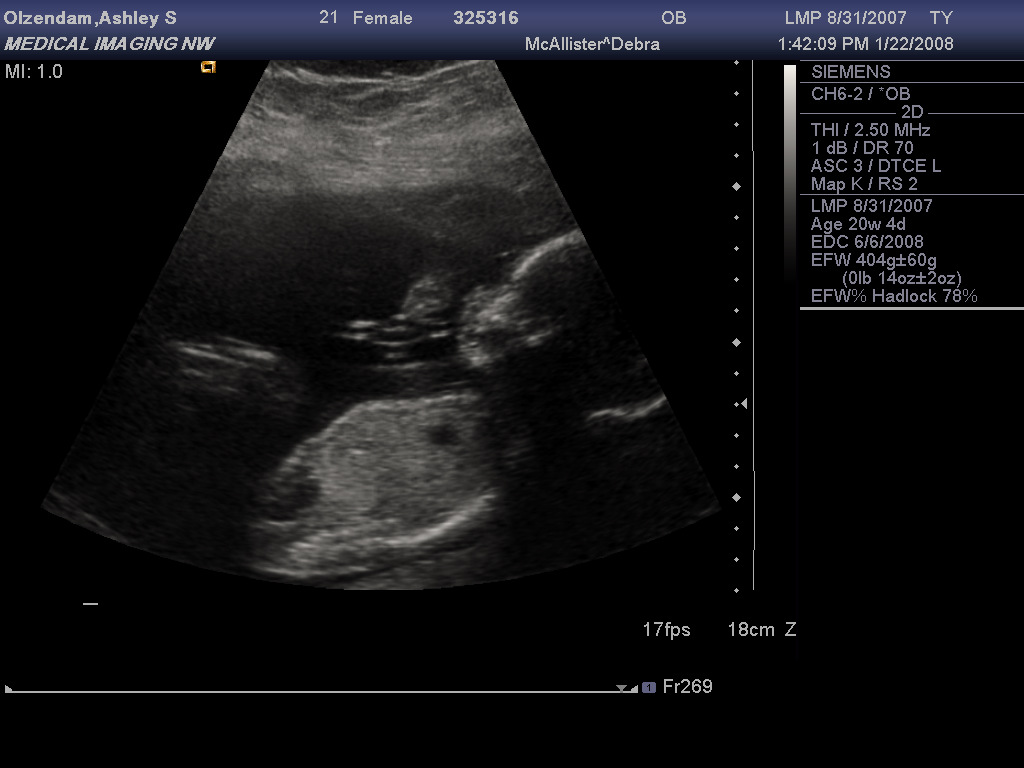

Had an ultrasound this afternoon and all the parts are where they should be. However, the baby was a bit uncooperative, and refused to part its legs for the technician to take a peek, so we're still unsure of the sex. I think Stiofain has been conspiring with the baby while I sleep (he didn't want to know). :lol:

Profile with  Arm.jpg

Clear Profile.jpg

In the top pic, the baby is so giving you the bird. :P